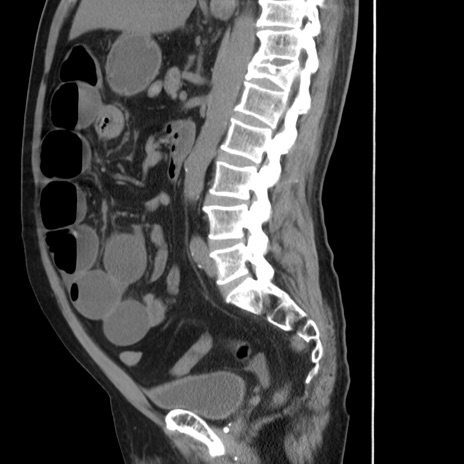

症例20(矢状断像)

【症例】 60歳代男性

【主訴】 腹部膨満、嘔吐

【現病歴】5日前頃より倦怠感を認め食事量減少し4日前の朝嘔吐、食事摂取困難となった。 3日前近医受診し点滴施行され整腸剤などを処方された。 当日他院を受診し、腹部膨満著明、炎症反応の上昇(CRP10.8、WBC11200)あり、紹介受診となる。

【身体所見】 意識JCS1 受け答えがはっきりしないBP 111/57mHg、 P 67bpm、、BT35.2°C、SpO2 97%(RA)、 腹部:膨隆、打診で鼓音あり、全体的に圧痛有り、腸蠕動音(-)、反跳痛ははっきりせず。

【データ】WBC 11400、CRP 14.20